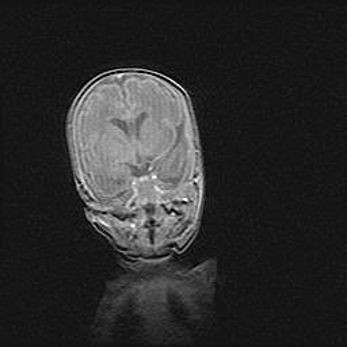

Открытая гидроцефалия.

Возраст: 9 месяцев 12 дней

Вес: 6800 г

Пол: мужской

Окружность головы: 41,5 см

Срок гестации: 28 недель

Гидроцефалия головного мозга у новорожденных имеет характерный признак: опережающий рост окружности головы приводит к визуально хорошо определяемой гидроцефальной форме сильно увеличенного в объёме черепа. Детские неврологи определяют следующие симптомы гидроцефалии у грудничков: выбухающий напряжённый родничок, частое запрокидывание головы, смещение глазных яблок к низу.